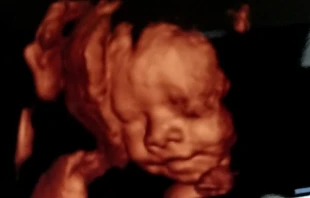

Para la CIDH una ecografía es un crimen mayor que el aborto

La Comisión Interamericana de Derechos Humanos (CIDH), que abiertamente se ha manifestado a favor de la despenalización del aborto en diversos países, expresó este 6 de octubre su “condena” por la realización de una ecografía a una madre adolescente durante la multitudinaria marcha “A favor de la mujer y de la vida”.

Ecografía “en vivo” desata furia de abortistas y se hace viral

La ecografía realizada a una madre adolescente con un bebé de 38 semanas de gestación, en el marco de la multitudinaria marcha “A favor de la mujer y de la vida”, desató la furia de defensores del aborto legal e hizo que el video se convierta en viral en Twitter.